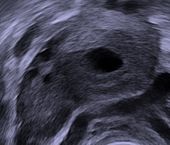

Vaginal ultrasound showing a corpus luteum in a pregnant woman, with a fluid-filled cavity in its center.